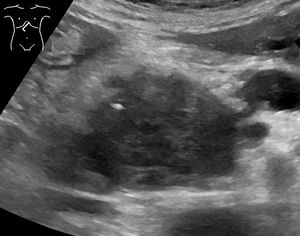

의학 영상 기술인 컴퓨터 단층 촬영(CT 스캔) 및 내시경 초음파 (EUS)는 진단을 확인하고 종양의 외과적 절제 가능성("절제 가능성")을 결정하는 데 사용된다.[4] 조영 CT 스캔에서 췌장암은 정상 췌장에서 보이는 빠른 소실이나 만성 췌장염에서 보이는 지연된 소실과 달리 점진적으로 증가하는 조영제 섭취를 일반적으로 보여준다.[56] 자기 공명 영상 및 양전자 방출 단층 촬영도 사용될 수 있으며,[3] 자기 공명 담관 췌장 조영술이 일부 경우에 유용할 수 있다.[54] 복부 초음파는 덜 민감하며 작은 종양을 놓치지만, 간으로 전이된 암과 복강 내 체액 축적(복수)을 식별할 수 있다.[4] 다른 기술 전에 빠르고 저렴한 첫 번째 검사에 사용할 수 있다.[70]

; 초음파 검사

: 일반적으로 건강 검진에 사용된다. 전형적인 췌관암은 경계가 불분명하고 불규칙한 저에코 영역으로 묘사된다. 췌두부의 암에서는 주췌관이나 담관의 확장도 관찰된다.